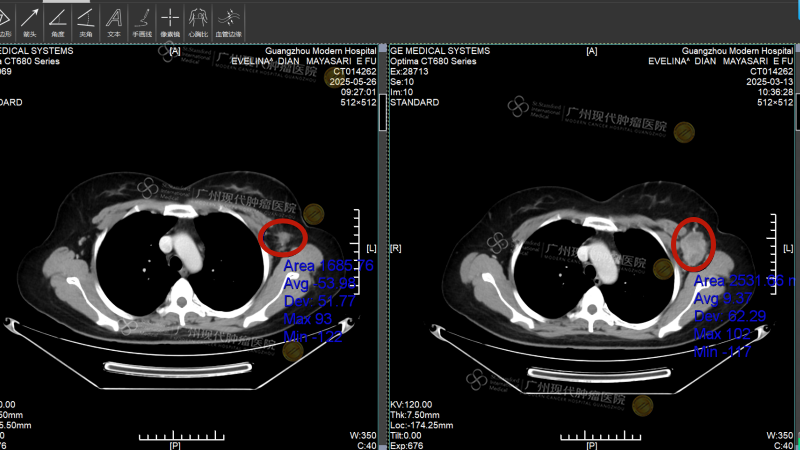

Pada Februari 2025, di tengah teriknya cuaca Kalimantan Tengah, Indonesia, Evelina tersiksa oleh muntah-muntah hebat yang terus berulang hingga tubuhnya kurus kering. Pemeriksaan di rumah sakit setempat menunjukkan adanya benjolan sebesar sekitar 6cm di payudara kirinya, disertai dengan metastasis besar di hati (sekitar 16cm), serta penyebaran ke kelenjar getah bening dan tulang. Hasil biopsi patologi menunjukkan: kanker payudara invasif, ER (-), PR (-), HER-2 (3+), Ki-67 90%.

Empat minggu kemudian, Intervensi kedua benar-benar membawa keajaiban: Tumor metastasis di hati menyusut dari 16cm menjadi sekitar 2 cm, asites menghilang, dan fungsi hati perlahan kembali normal. Pemeriksaan pencitraan ulang menunjukkan: benjolan di payudara dan lesi di hati menyusut drastis, sebagian bahkan mengalami nekrosis. Saat Evelina mengambil foto liburan di pinggir jalan Guangzhou dan mengirimkannya kepada teman-teman di kampung halamannya, balasan yang ia terima semuanya sama:“Kamu yakin diagnosisnya tidak salah? Ini tidak terlihat seperti pasien kanker!”

Sebelum pengobatan, tumor payudara berukuran 2cm; setelah pengobatan, tumor menghilang

Sebelum pengobatan, tumor hati berukuran sekitar 16cm; setelah pengobatan, tumornya telah kehilangan aktivitas